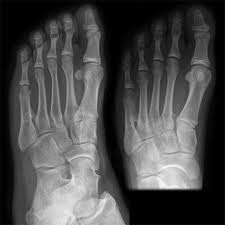

Signs Of Bone Cancer In The Foot / Bump On Top Of Foot Causes Diagnosis And Treatment - They may arise from the bone tissue, and we call them primary bone tumors.. Bone tumors can be of two different types. Pain in the affected bone is the most common sign of bone cancer. Of these bone tumors in the foot, only a fraction occur within the heel. Your red blood cell levels may drop, causing anemia. Bone cancer is a fairly rare disease, so if you've developed bone pain, don't jump to conclusions.

Cureus Chondromyxoid Fibroma Of Distal Phalanx Of The Great Toe A Rare Clinical Entity from assets.cureus.com Pain is usually the first symptom of bone cancer. Secondary malignant bone tumors are estimated to be 50 to 100. Pain is the most common sign of bone cancer, and may become more noticeable as the tumor grows. The color is different from the rest of your skin. The affected leg or joint develops pain that is often described as consistent and dull, like a persistent ache. While this means that tumors in the heel are quite rare, it doesn't mean that this diagnosis should be excluded from the realm of possible causes of your. Bone cancer is often fatal in dogs, though surgical removal of affected bone is sometimes possible and can save dogs' lives. Bone cancer is a fairly rare disease, so if you've developed bone pain, don't jump to conclusions.

Bone cancer is often fatal in dogs, though surgical removal of affected bone is sometimes possible and can save dogs' lives. Early on, the pain may only occur at night, or when you are active. This type of pain is usually characterized as burning, itching, or radiating. Bone metastasis may be the first sign that you have cancer, or bone metastasis may occur years after cancer treatment. Symptoms of a bone tumor in your foot bone tumors of the foot may be painless. Know the signs and symptoms of bone cancer. Each of these types of cancer has their own set of symptoms and treatment, but the main symptom in all of these is a swelling or ulcer on the foot or toe. This tumor deserves extra attention and study for several reasons. Pain is the most common sign of bone cancer, and may become more noticeable as the tumor grows. Additionally, if the tumor is in the leg, a limp or other walking difficulties may occur. Initially, it will be mild and intermittent, often occurring at night or after engaging in physical activity. Bone tumors can be of two different types. Any bone can be affected, although bone cancer most often develops in the long bones of the legs or upper arms.

Bone pain pain caused by bone cancer usually begins with a feeling of tenderness in the affected bone. This gradually progresses to a persistent ache or an ache that comes and goes, which continues at night and when resting. Of these bone tumors in the foot, only a fraction occur within the heel. Bone that is already weakened by a tumor can break, causing severe pain. Your red blood cell levels may drop, causing anemia. Foot or toe cancer (digital and soft tissue cancer), which can include squamous cell carcinoma, melanoma, osteosarcoma, mast cell tumor, and malignant soft tissue sarcoma is common in dogs. Symptoms of a bone tumor in your foot bone tumors of the foot may be painless. Bone cancer is rare, making up less than 1 percent of all cancers. Possible symptoms of bone cancer include: Find out from our team of experts how bone cancer is detected, diagnosed, and staged. Initially, it will be mild and intermittent, often occurring at night or after engaging in physical activity. Bone cancer is often fatal in dogs, though surgical removal of affected bone is sometimes possible and can save dogs' lives. Pain is usually the first symptom of bone cancer.

Bone metastasis can cause pain and broken bones. Pain is the most common sign of bone cancer, and may become more noticeable as the tumor grows. Any bone can be affected, although bone cancer most often develops in the long bones of the legs or upper arms. 1 bone pain one of the most frequent symptoms associated with bone cancer is bone pain. Initially, it will be mild and intermittent, often occurring at night or after engaging in physical activity. (9) in some series it is the single most common sarcoma of any type in the distal lower extremity. Osteoid osteoma often happens in long bones, usually in your early 20s. 12 warning signs of bone cancer you should not ignore. Signs of anemia are tiredness, weakness, and shortness of breath. Possible symptoms of bone cancer include: With rare exceptions, cancer that has spread to the bones can't be cured. The affected leg or joint develops pain that is often described as consistent and dull, like a persistent ache. Pain in the affected bone is the most common sign of bone cancer.